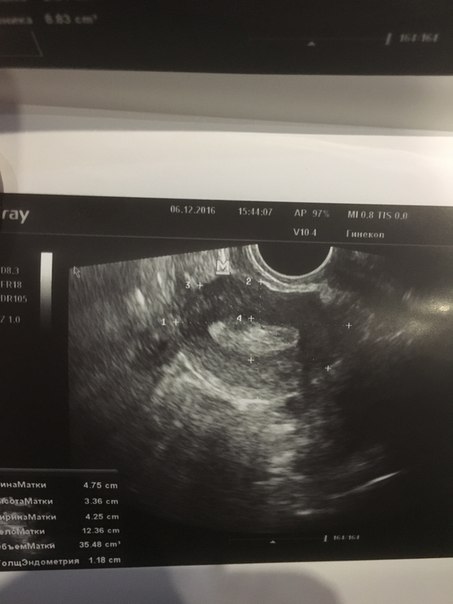

Помогите кто нибудь.Нет деток и никакого аборта ни викидыша ничего 5 лет.живу с мужем.мне 22.все эти 5 лет по врачам по больницам.в сентябре была чистка.на днях на УЗИ .сказали все плохо срочно что то делать иначе климакс в 23 года.что делать неужели это конец приложу результаты УЗИ и гормонов.может кто сталкивался.поделитесь

Я 6 шт фолликов насчитала в яичнике, очень хороший эндометрий,при чем тут климакс ( странный доктор)??? Проблема в гормонах, снижайте пролактин и рожайте на здоровье)))

Они не лопаются и не созревают.доктор говорит что яичники спят и не работают.кровотечение по месяцу идет из за поликистоза.жду анализа на оставшийся резерв фолликулов.так как она говорит что яичники пусты лишь железистая ткань

И эндометрий у меня 12 мм это толстенный эндометрий гиперплазия

У меня 6 день цикла был когда делала УЗИ.Останавливали кровотечение регулоном.кровь месяц лила.

Да поставила поликистоз

И под вопросом полип и гиперплазия